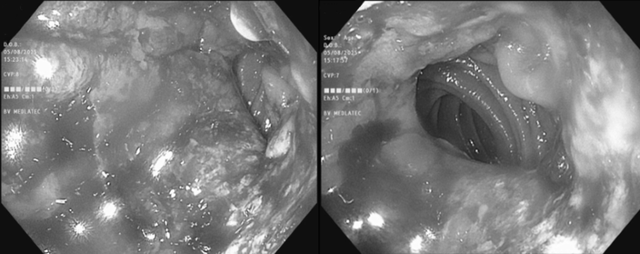

Hình ảnh nội soi dạ dày của bệnh nhân phát hiện bất thường. Ảnh: BVCC

Đặc biệt, trên hình ảnh nội soi dạ dày phát hiện dạ dày đã cắt bán phần, phần còn lại và miệng nối phù nề sung huyết kèm nhiều trợt loét dễ chảy máu khi bơm hơi, tiến hành sinh thiết 4 mảnh tại bờ ổ loét làm xét nghiệm mô bệnh học.